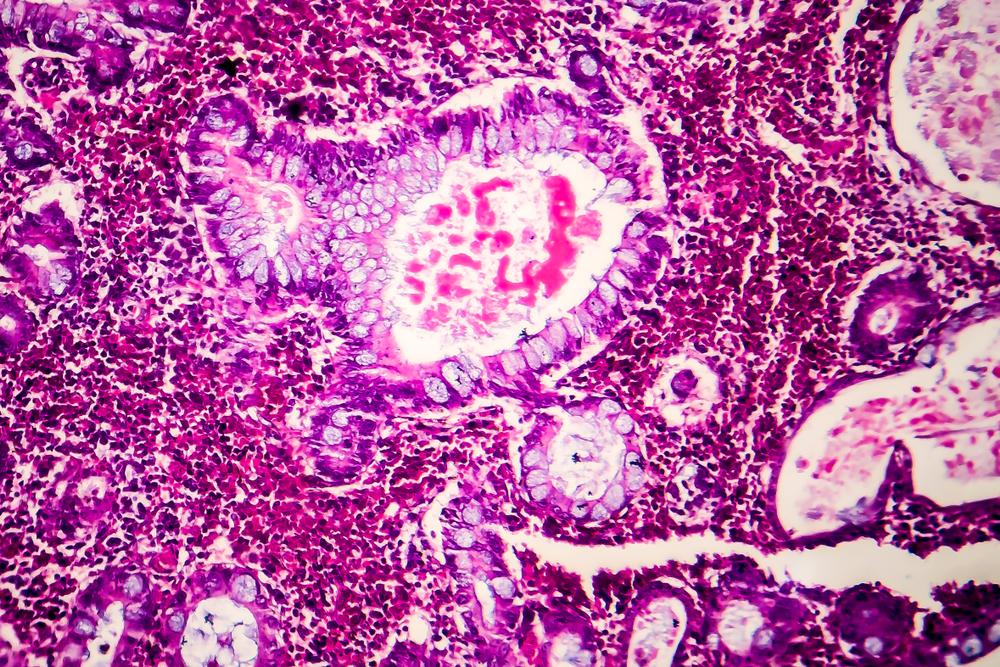

Villous adenomas are abnormal growths that develop in the lining of the colon. They are considered precancerous, meaning they have the potential to become malignant over time. Unlike other types of polyps, villous adenomas tend to grow larger and may have a flatter, broader shape.

Not all polyps turn into cancer, but villous adenomas carry a higher risk than some other types. They are most commonly found in the rectum and sigmoid colon. Understanding what they are helps patients and caregivers take the necessary steps for monitoring and prevention.